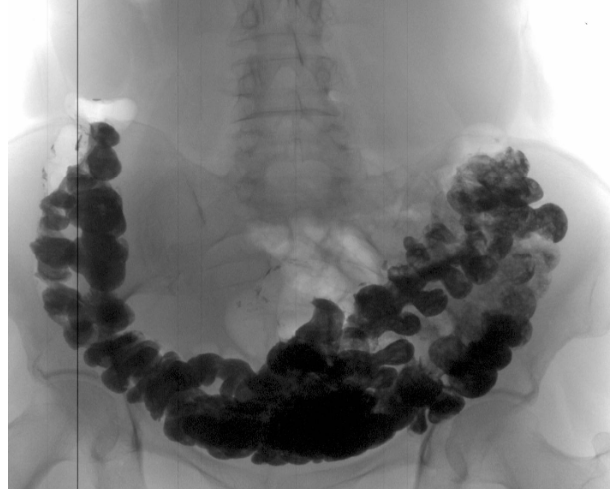

Наприклад, хронічний гастрит або виразкова хвороба можуть призвести до появи запальних змін в шлунковій стінці, що можуть бути передраковими утвореннями. Неусунення запорів або діареї може призвести до пошкодження слизової оболонки кишечника та збільшити ризик розвитку раку кишечника.

Більшість симптомів раку кишечника проявляються досить явно, і їх важко не помітити. У пацієнтів із цим захворюванням на початковій стадії часто з'являються:

- закрепи;

- сильне газоутворення та метеоризм ;

- печія;

- кислотний рефлюкс;

- проблеми із ковтанням;

- нудота блювота;

- діарея та часті симптоми розладу шлунка.